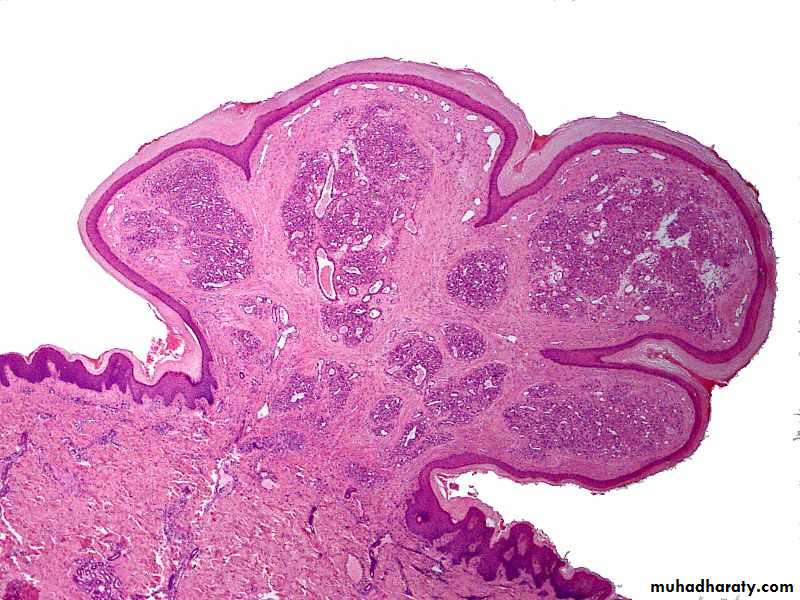

• Papilloma

• A papilloma is a benign epithelial neoplasm composed of fingerlike projections of squamous epithelium.

• Oral and oropharyngeal papillomas may occur as single or multiple, sessile, warty lesions, seldom measuring more than a few millimeters.

• When they involve the oropharynx, the soft palate and the uvula are the usual sites.

• The histology of a papilloma shows fingerlike projections of squamous epithelium above the level of the surrounding mucosa.

• Management consists of surgical excision. Recurrences are rare.